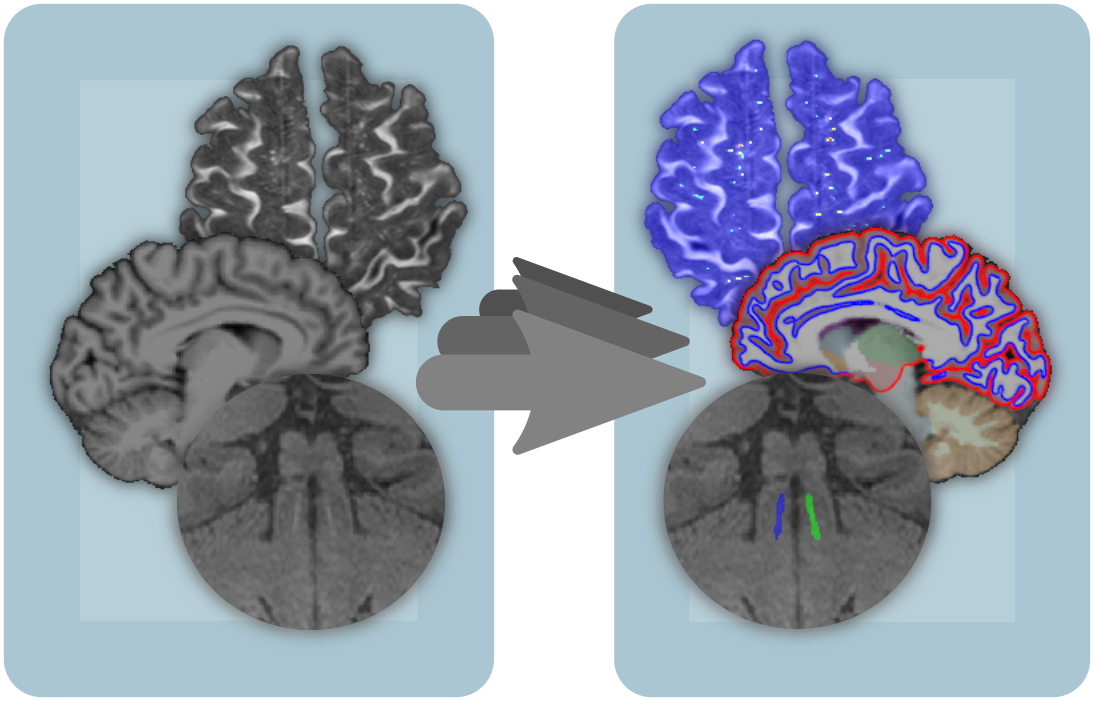

The MedDigit team pursues the goal of a continuous registration and quantitative analysis of brain structure and function of all patients with neurological and neuropsychiatric disorders in Saxony-Anhalt. The team develops a fully automated digital system for processing clinical brain data from the Department of Neurology and external caregivers (MRI/MEG/EEG) as well as for deriving biomarkers for defined neurological disorders. The system comprises components for ensuring comparability of data that were acquired in a non-standardized way, for the automated digital analysis and enhancement of data quality, the automated feature extraction and data classification as well as the determination of clinically relevant, quantitative biomarkers.